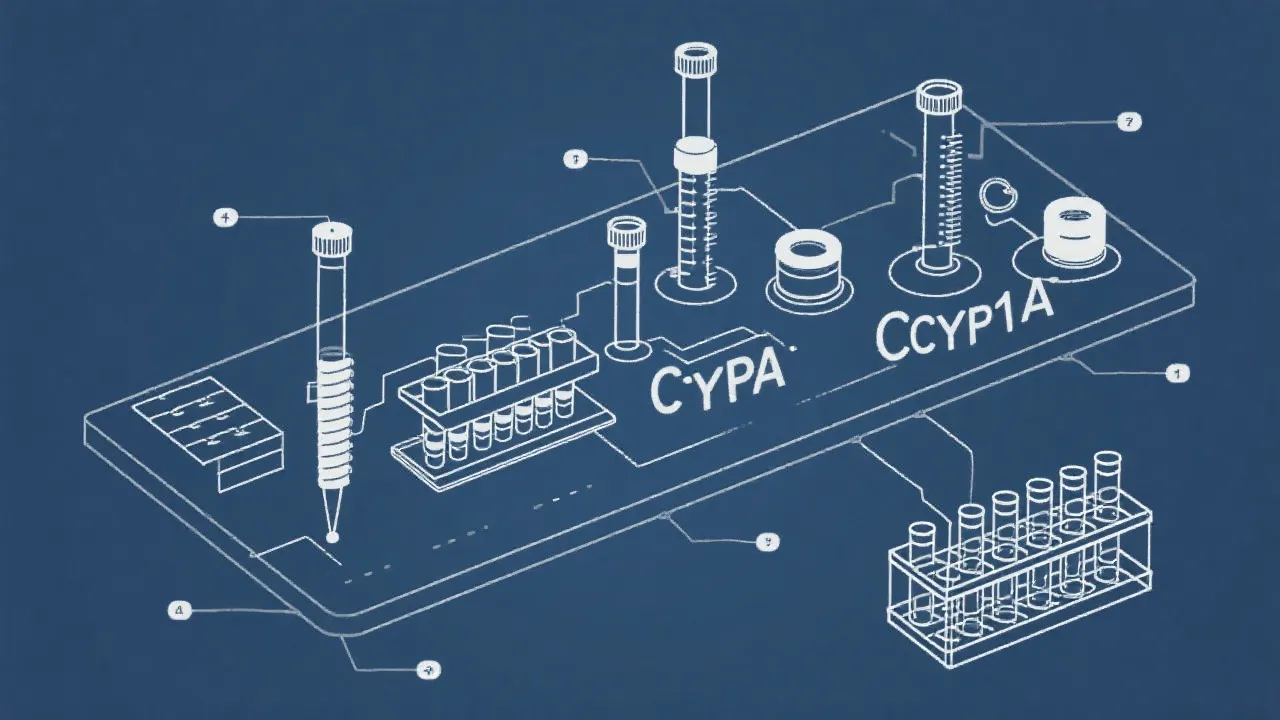

Understanding the Cyp1a1 Assay

Understanding the Cyp1a1 Assay

Understanding Cyp1a1 Assay Techniques

Understanding the Cyp1a1 Assay's Role

Understanding the Cyp1a1 Assay

Understanding the Cyp1a1 Assay

Understanding the Cyp1a1 Assay Process

Understanding Cyp1a1 Assay Methods

Understanding Cyp1a1 Assay Techniques

Understanding Cyp1a1 Assay Techniques

Understanding the Cyp1a1 Assay

Understanding Cyp1a1 Assay in Research